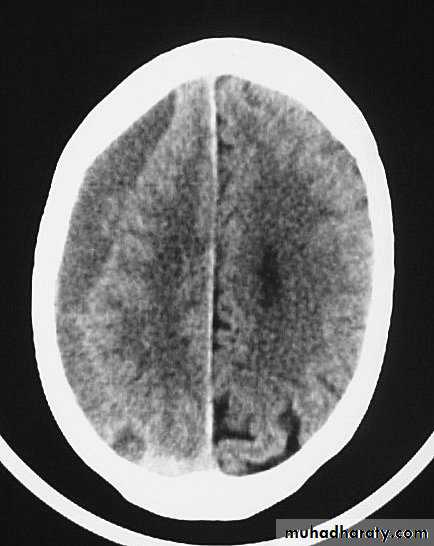

c. Intracerebral Haematoma

This is the least common of traumatic haematoma.

They are due to areas of traumatic contusion coalescing into a contusional haematoma.

Disrupted cerebral tissue release thromboplastins that potentiate haemorrhage.

CT scan: appear as hyperdence lesions with associated mass effect and midline shift.

Large intracerebral haematomas should be evacuated unless the patient’s neurological state is improving.

Small inracerebral haematomas may not require removal, but be aware that they can expand.